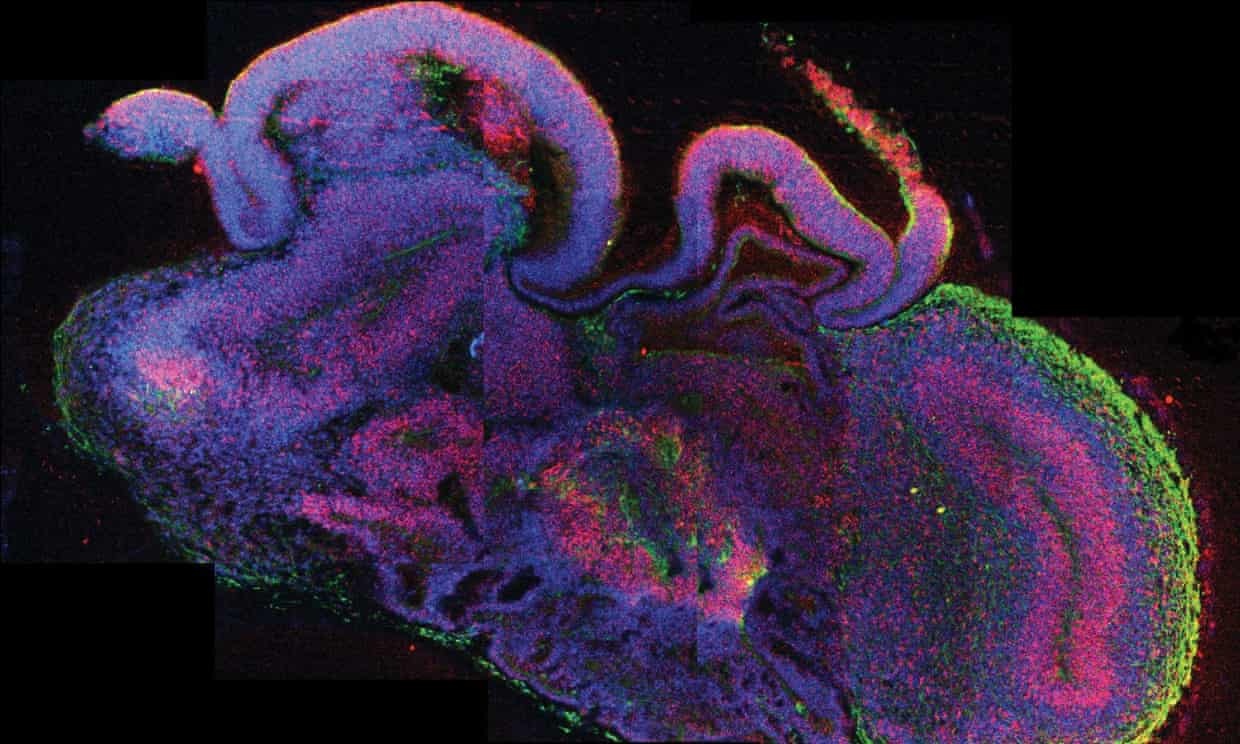

| Mặt cắt một mô não người nhân tạo. Ảnh: EPA. |